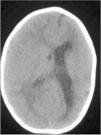

En la tomografía computarizada craneal (TCC) existe una asimetría entre ambos hemisferios cerebrales: el hemisferio izquierdo (HI) es de menor tamaño, con ventrículo lateral (VL) moderadamente dilatado. El hemisferio derecho (HD) sobrepasa la línea media y el VL derecho es de dimensiones normales (fig. 1 y 2).

En la resonancia magnética (RM) craneal se evidencia el mayor tamaño del HD, que presenta un área de mayor brillo en T2 y Flair localizada en la sustancia blanca parietal posterior, mayor tamaño de la región derecha del troncoencéfalo respecto a la izquierda y polimicrogiria en el HI, junto con las alteraciones morfológicas ya visibles en la TCC (fig. 4).